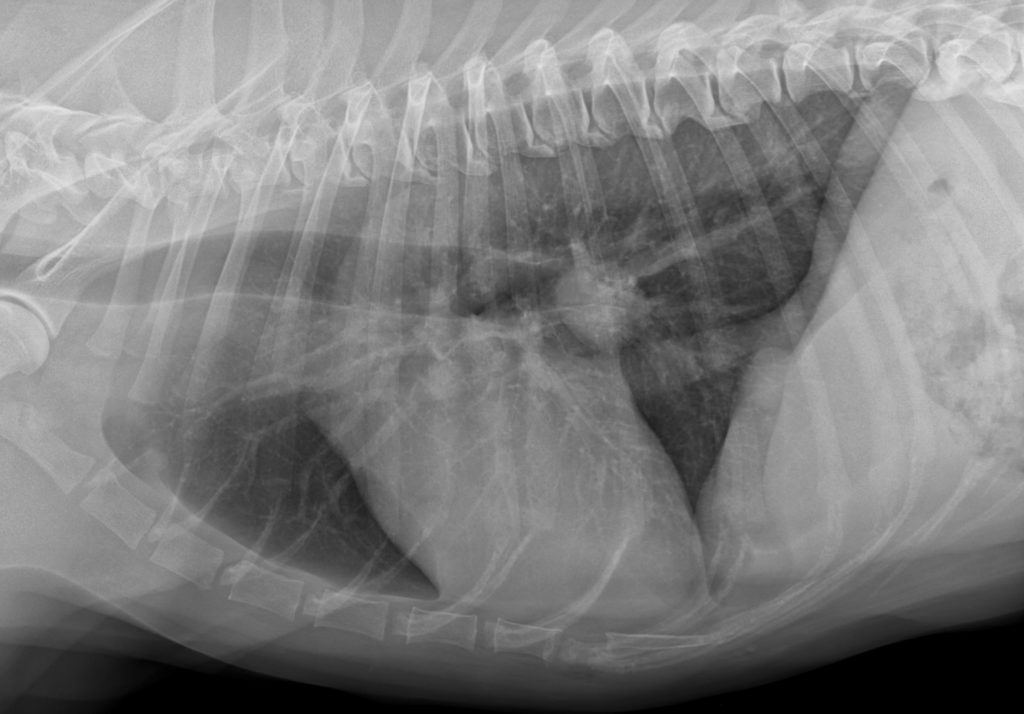

Lungen CT und Volumentomografie der Lunge beim Hund beim unklaren